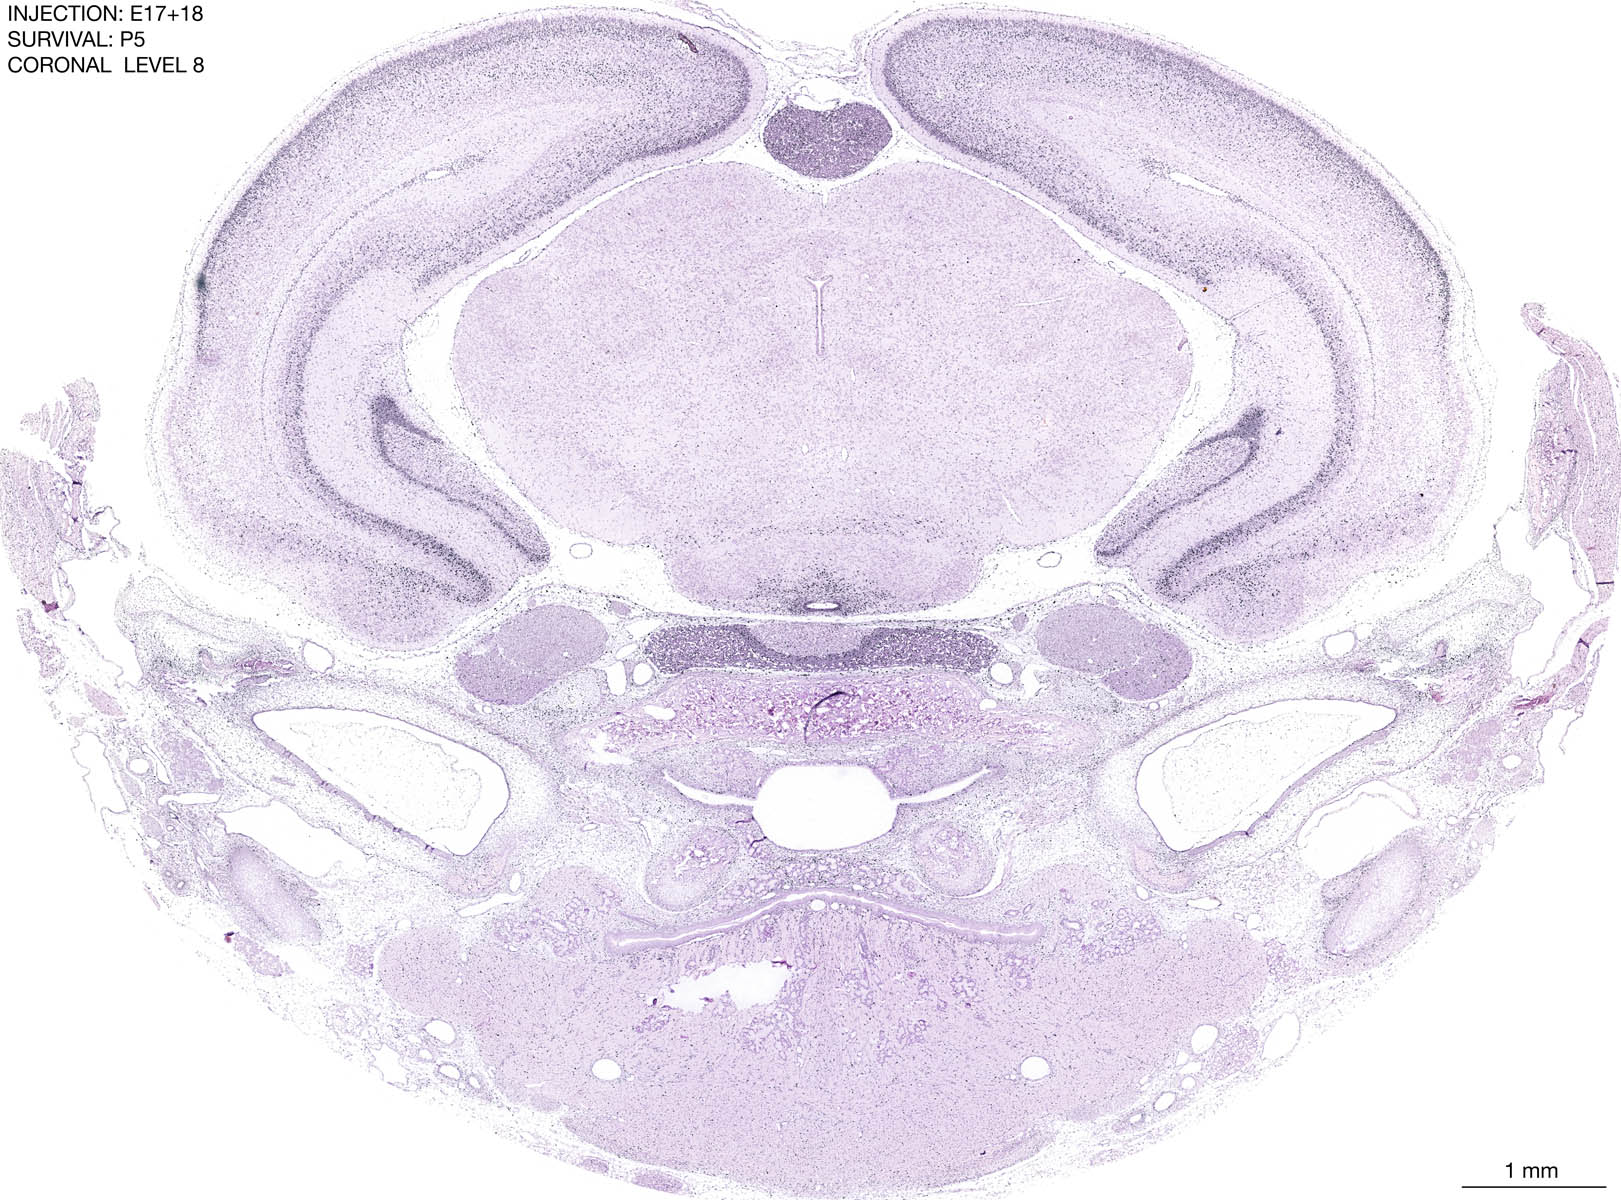

E17+18 P5 Survival The images below are from the brain of a rat that was exposed to tritiated thymidine on E17+18 and survived to P5. Download: Large | High Res Download: Large | High Res Download: Large | High Res Download: Large | High Res Download: Large | High Res Download: Large | High Res Download: Large | High Res Download: Large | High Res Download: Large | High Res Download: Large | High Res Download: Large | High Res Download: Large | High Res Download: Large | High Res Download: Large | High Res Download: Large | High Res Download: Large | High Res Download: Large | High Res Download: Large | High Res Download: Large | High Res Download: Large | High Res Download: Large | High Res Download: Large | High Res Download: Large | High Res Download: Large | High Res Download: Large | High Res Download: Large | High Res